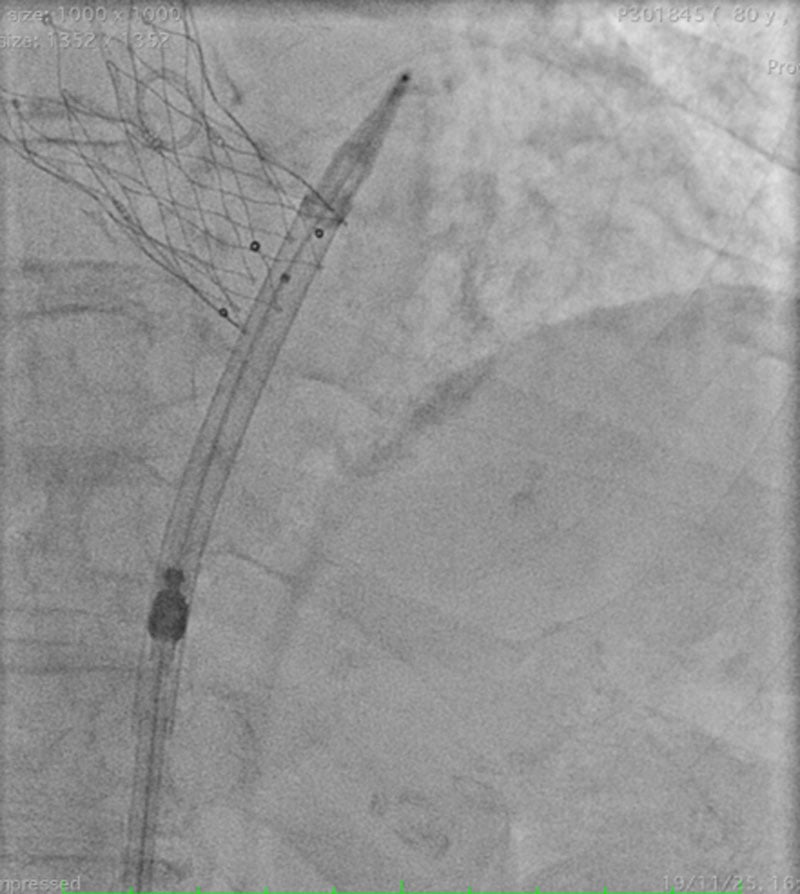

A 0.035” stiff wire can be inserted in parallel, through the integrated sheath of the Navitor THV (Video 2). The wire can traverse the sheath only when the valve capsule is not fully retracted against the distal tip of the sheath (Figure 2, Video 3).

Figure 2